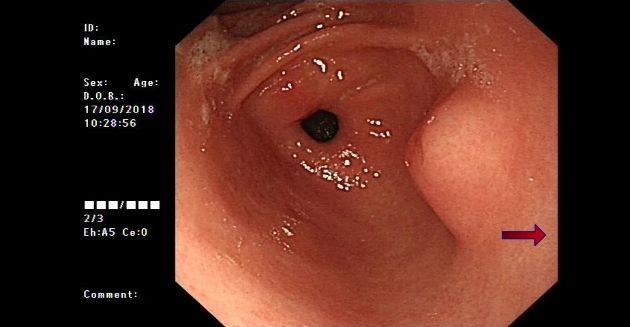

In 2018, she was diagnosed with chronic gastritis and a submucosal bulging mass on the lesser curvature of the gastric antrum by gastroscopy (Figure 1).

Figure 1. Gastroscopy revealed a submucosal bulging mass on the lesser curvature of the gastric antrum.

Figure 2. Ultrasound endoscopy indicated a submucosal bulging mass on the lesser curvature of the gastric antrum (red arrow)